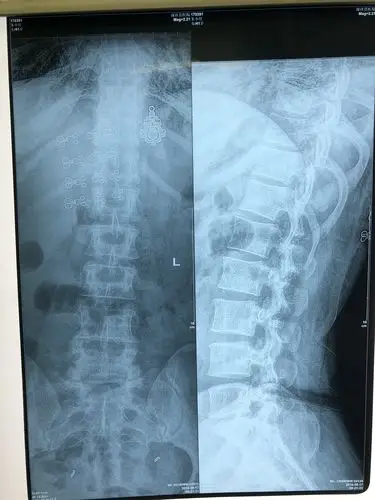

腰间盘突出图片大家进来看看是什么原理